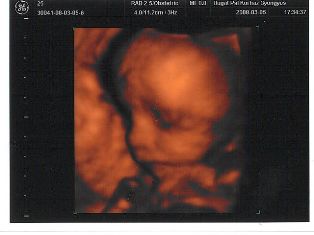

Mátét láthatjátok.

Nagyon szép baba...te vagy az aki biztos lehet benne,hogy nem kell rózsaszín ruha,és lány név :D :D :D :D :D

Melike, nagyon édes Máté baba:)

Melike, nagyon jók a képek Mátéról!!! :lol:

Nagyon jok a 4d uh-os képek. Gigi!!! a táblázatba nem lehetne beszerkeszteni mindenkinek egy uh-os képet??? ( picibe) Ez csak egy gondolat volt. :wink: